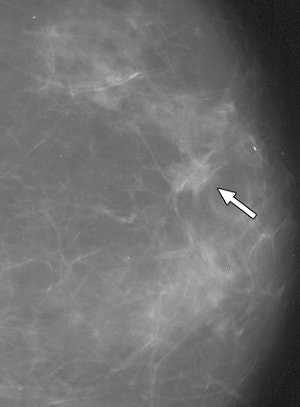

| False-negative case for all reviewers: 76-year-old woman with invasive ductal carcinoma. Above, craniocaudal mammogram obtained four years before study in which mass (arrow) was excised and was found to be benign (fibrocystic changes without atypia) at histology. Middle, screening mammogram, craniocaudal view, two years before study shows postsurgical changes. Below, screening mammogram, craniocaudal view, at time of study in which increase in density at biopsy site was not detected by any of reviewers, although area was marked by CAD system. |